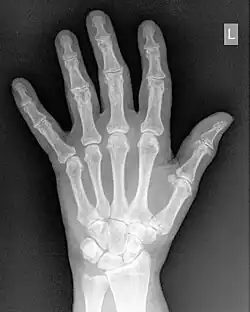

- An example of a Look-Up Table (LUT) which can be used for contrast enhancement is illustrated in Figure 5.5. The process is controlled typically by two controls on the console of the digital image processor - the Level and Window. It should be noted that variations in the names for these controls, and in their exact operation, can exist with different systems but the general approach described here is sufficient for our purposes. It is seen in the figure that the level controls the threshold value below which all pixels are displayed as black and the window controls a similar threshold value for a white output. The simultaneous use of the two controls allows the application of a gray-level window, of variable width, which can be placed anywhere along the gray scale. Subtle gray-level changes within images can therefore be enhanced so that they are displayed with greater clarity - see Figure 5.6.

- Contrast enhancement can also be effected through manipulation of the image's statistical histogram and is illustrated in Figure 5.8. A histogram is a plot of the frequency of occurrence of each pixel value in an image - see panel (a) for an example, where this frequency is plotted as a function of pixel value. It can be seen that pixels from the black surroundings of the hand are indicated by the peak at low pixel values. It can also be seen that the pixel values representing bone and tissue attenuation form a broad range of lower frequencies extending to just over half the grey scale. Indeed the pixels of the 'L' marker can be seen to form an isolated blip at a pixel value of 75. Note that the term frequency as used here should not be confused with the term spatial frequency we have been using in our discussion of Fourier techniques.

- Manipulating such histogram data can be used for contrast enhancement by redistributing the pixel values to generate, for instance, a better utilisation of the grey scale. The process of Histogram Equalisation is illustrated in the Figure 5.8, panel (b) along with its histogram - panel (c). It can be seen that the process broadens the frequency distribution so that it now spans the full range of the grey scale. Notice also that the process can generate absent pixel values.:Manipulating such histogram data can be used for contrast enhancement by redistributing the pixel values to generate, for instance, a better utilisation of the grey scale. The process of Histogram Equalisation is illustrated in the Figure 5.8, panel (b) along with its histogram - panel (c). It can be seen that the process broadens the frequency distribution so that it now spans the full range of the grey scale. Notice also that the process can generate absent pixel values.